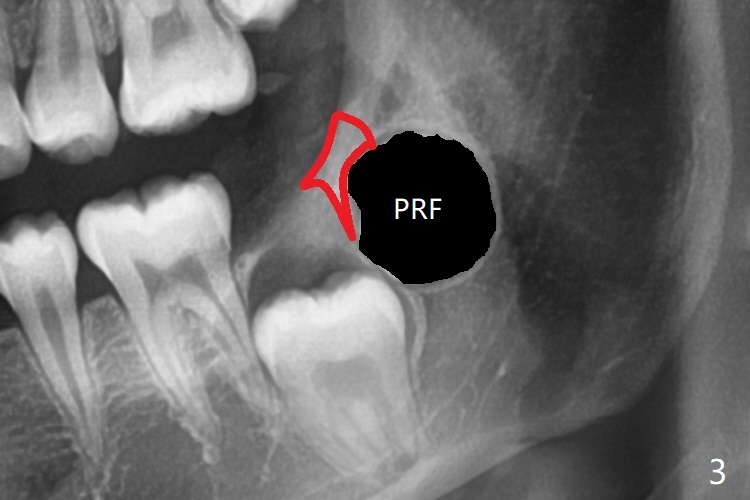

Treatment planning of surgical access to the impacted 7 (Fig.1) before CT analysis (to be canceled due to finance) include extraction of 8 (Fig.2) and removal of the bone coronal to 8 (Fig.3 red) so that there will be no bony block to 7 eruption (Fig.4). Place PRF or collagen plug in 8 socket to facilitate healing (Fig.3). Attach a retraction chain to the occlusal or buccal surface of 7 (Fig.6 pink) whenever it is convenient in term of hemorrhage and access (as mesial as possible). Remove 16 niti wires for brushing when the patient arrives. Cut 18 ss wire longer in the LL end (Fig.6 green to be bent to hook power chain (yellow)). Incision is shown as red in Fig.5. After 3 month delay, the thick buccal plate is removed from LL8 (1st) and 7 (2nd in sequence, as compared to Fig.2) to expose these unerupted teeth. In fact CT is not taken to decrease budget on the divorcing parents. A retraction chain is placed before extraction of LL8 with an intention to reduce hemorrhage (Fig.7). Although extraction requires several sectioning of the tooth, hemorrhage is mild to moderate. Instead of PRF and sticky bone (as compared to Fig.3), Osteogen plug is placed in the socket (Fig.8 OP). The bony septum between the 2 sockets is intentionally kept in place (*). 事实的确这样发生(图九:*)。埋伏牙不仅上移(^),而且远中移动(>),因为牵引方向(红虚线(橡皮筋),挂在上牙弓丝(图九:20ss:图十:18ss(之前))远端勾,积极牵引三个星期)。下次左上7放置舌侧纽扣,让病人更换橡皮筋。其实纽扣粘不住,上牙弓丝远中勾也不现实,只能使用橡皮筋挂在左上6,经常断。术后6个月,左下7继续上移(图十一)。这种低效率牵引仍然有效,牙齿继续上移,牙根长长(图十二:空箭头),但是受到左下6远中阻挡(*),所以下次在左上7咬合面装置舌侧纽扣和closed spring,改善牵拉方向(红箭头)。